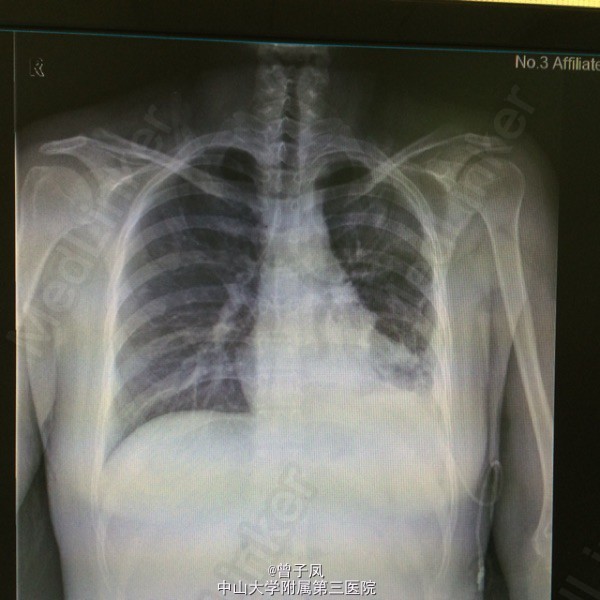

随访:抗结核治疗后复查肝功能无明显异常,复查胸片示胸水无增多,遂予带药出院,嘱其结核病院继续治疗。 讨论:胸腔积液病因以结核性或肿瘤性多见。肿瘤性积液多见于中老年患者,且胸水为血性多见;结核性多见于年轻患者,多伴有结核病全身表现,胸水多为浅黄色或淡绿色。该病例中,患者年轻、有低热、咳嗽,胸水为渗出性且以淋巴细胞为主,虽无病原学检查支持,但据临床经验还是给与抗痨治疗。